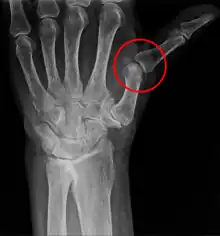

X-ray showing metacarpophalangeal subluxation of the thumb of a 71-years old woman due to trapeziometacarpal osteoarthritis

A subluxation of a joint is where a connecting bone is partially out of the joint.[5] In contrast to a luxation, which is a complete separation of the joint, a subluxation often returns to its normal position without additional help from a health professional.[6] An example of a joint subluxation is a nursemaid's elbow, which is the subluxation of the head of the radius from the annular ligament. Other joints that are prone to subluxations are the shoulders, fingers, kneecaps, ribs, wrists, ankles, and hips affected by hip dysplasia. A spinal subluxation is visible on X-rays and can sometimes impinge on spinal nerve roots, causing symptoms in the areas served by those roots. In the spine, such a displacement may be caused by a fracture, spondylolisthesis, rheumatoid arthritis,[7] severe osteoarthritis, falls, accidents and other traumas.